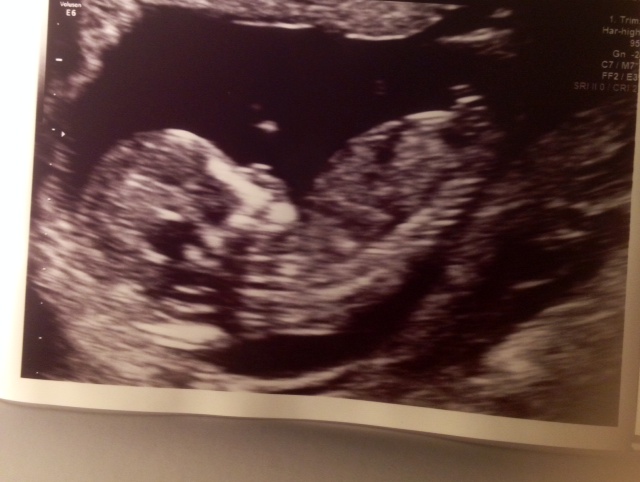

the thing sticking up is part of the leg, so I find it very hard to see. We are hoping on a girl but will of course love the child no matter what gender ;) can anyone see which gender it is based on this photo and how?

Sorry I can't see the nub.

Sorry, I'm having trouble making out a clear nub in this pic. Congratulations though and fingers crossed for your girl x

That's too close to spine for nub I am sorry to say I think boy as I see something sticking up if I have permission I could upload your photo to edit and show you then delete your photo x

No nub visible. Sorry! But I would guess girl based on skull shape but that's not very reliable. Congrats!